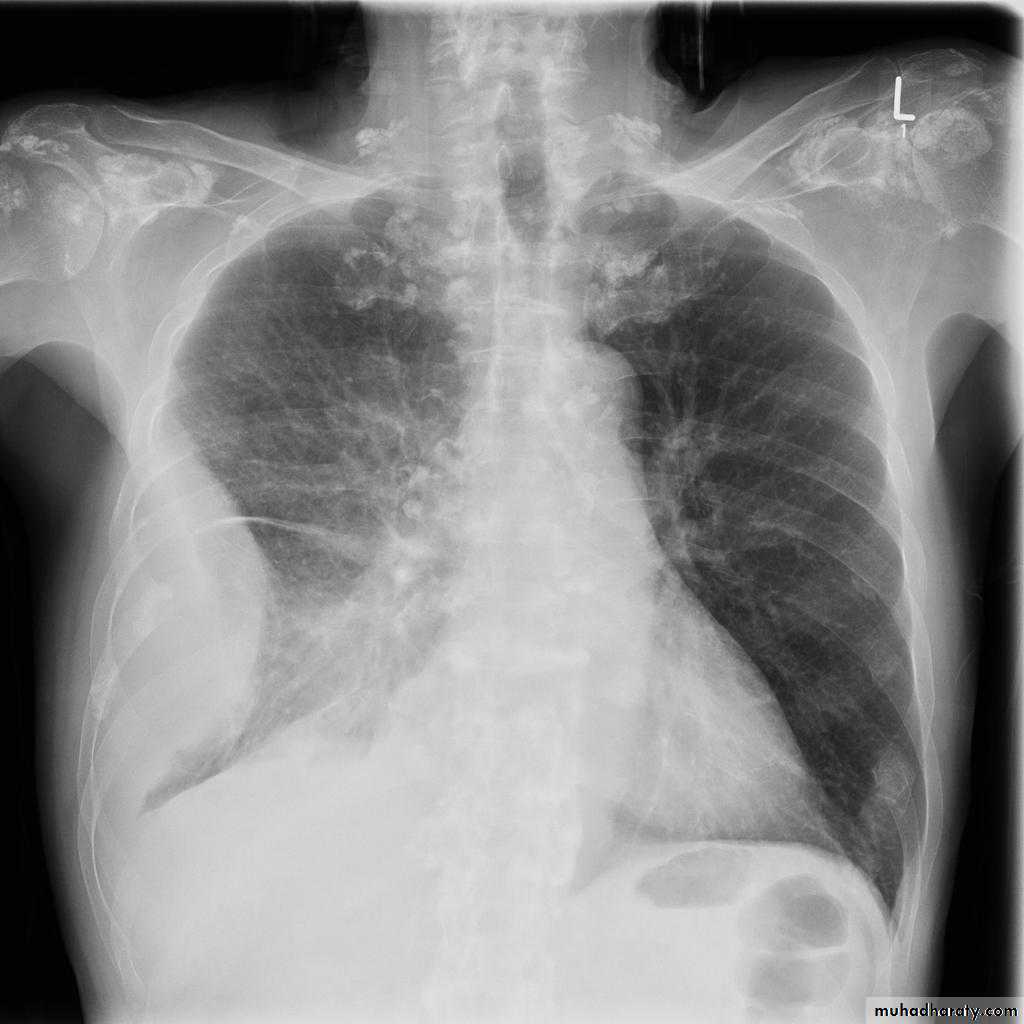

Bronchiectasis

59.Bronchiactasis